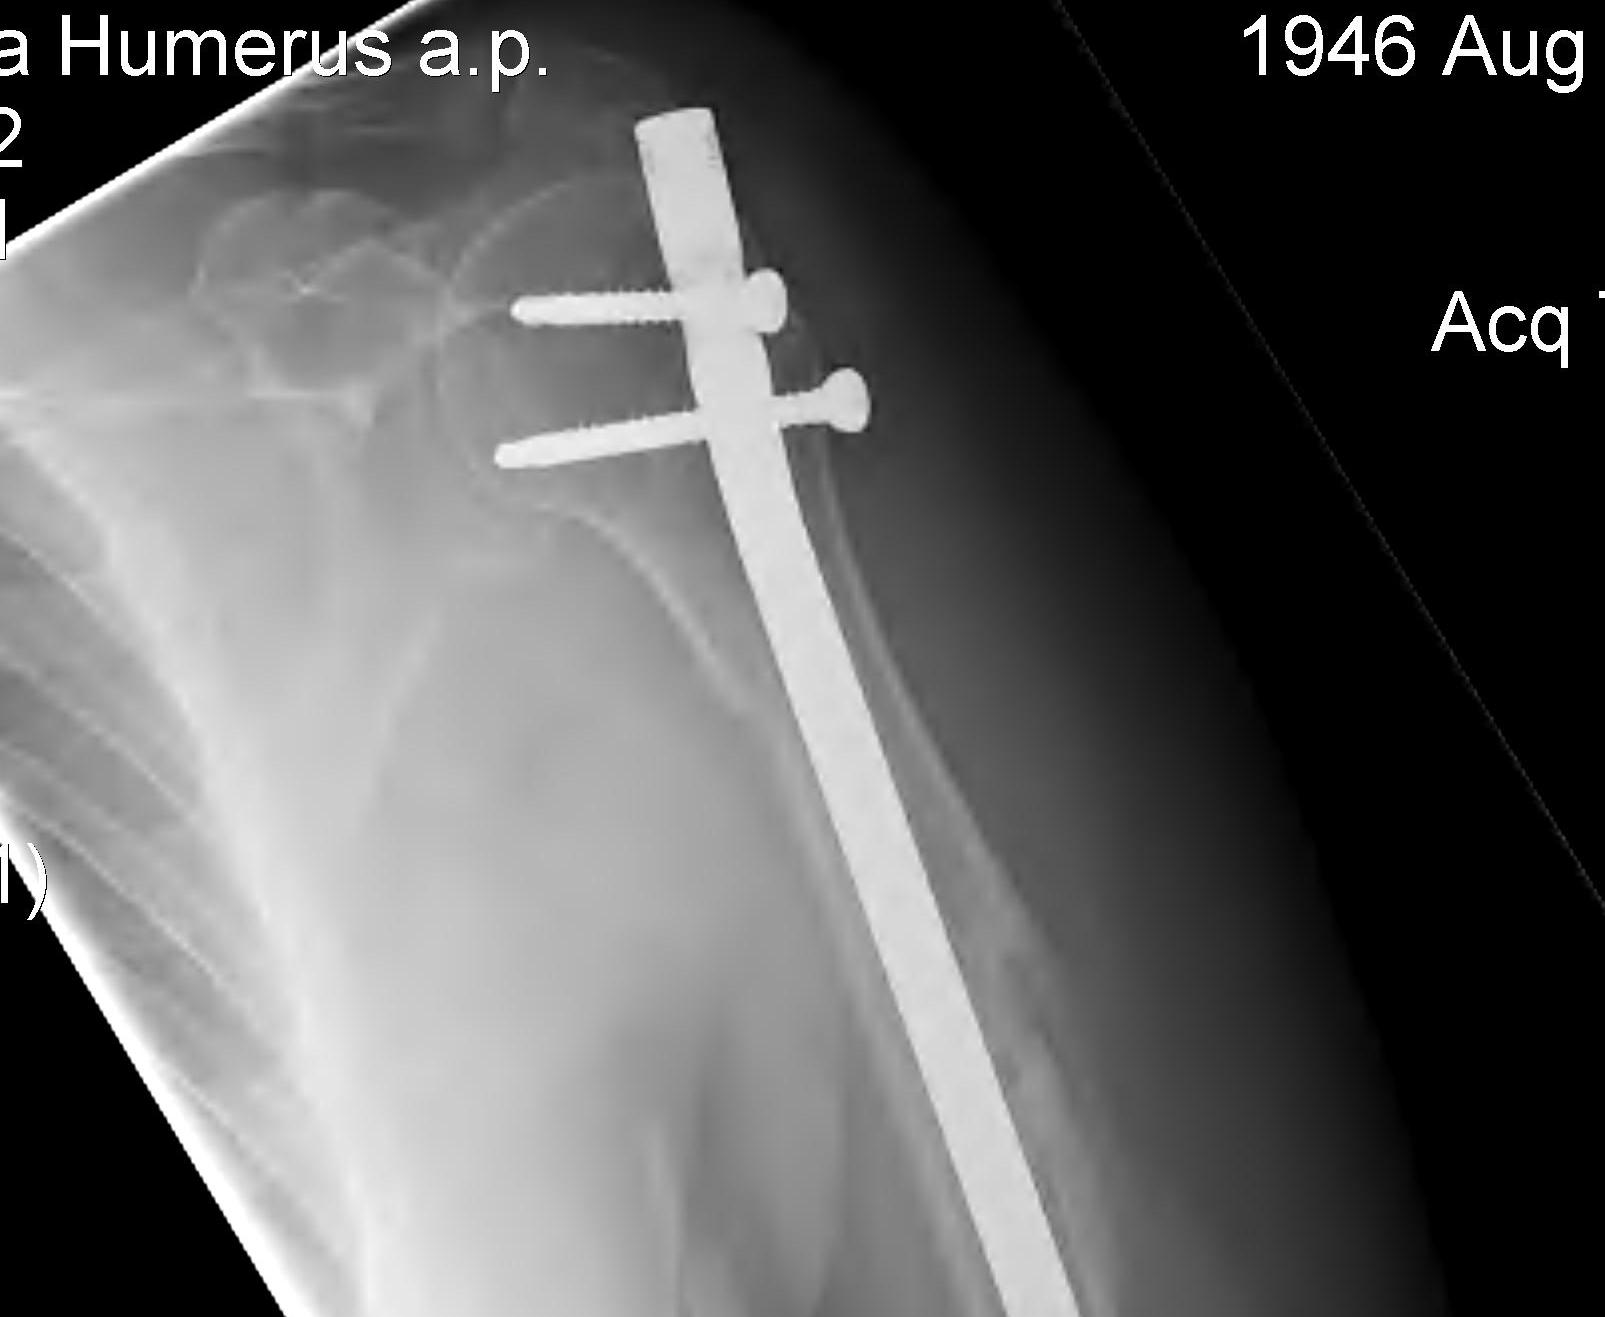

Humeral Fracture SegmentalHumeral Plate LateralHumeral Plate Long AP

Segmental fracture ORIF